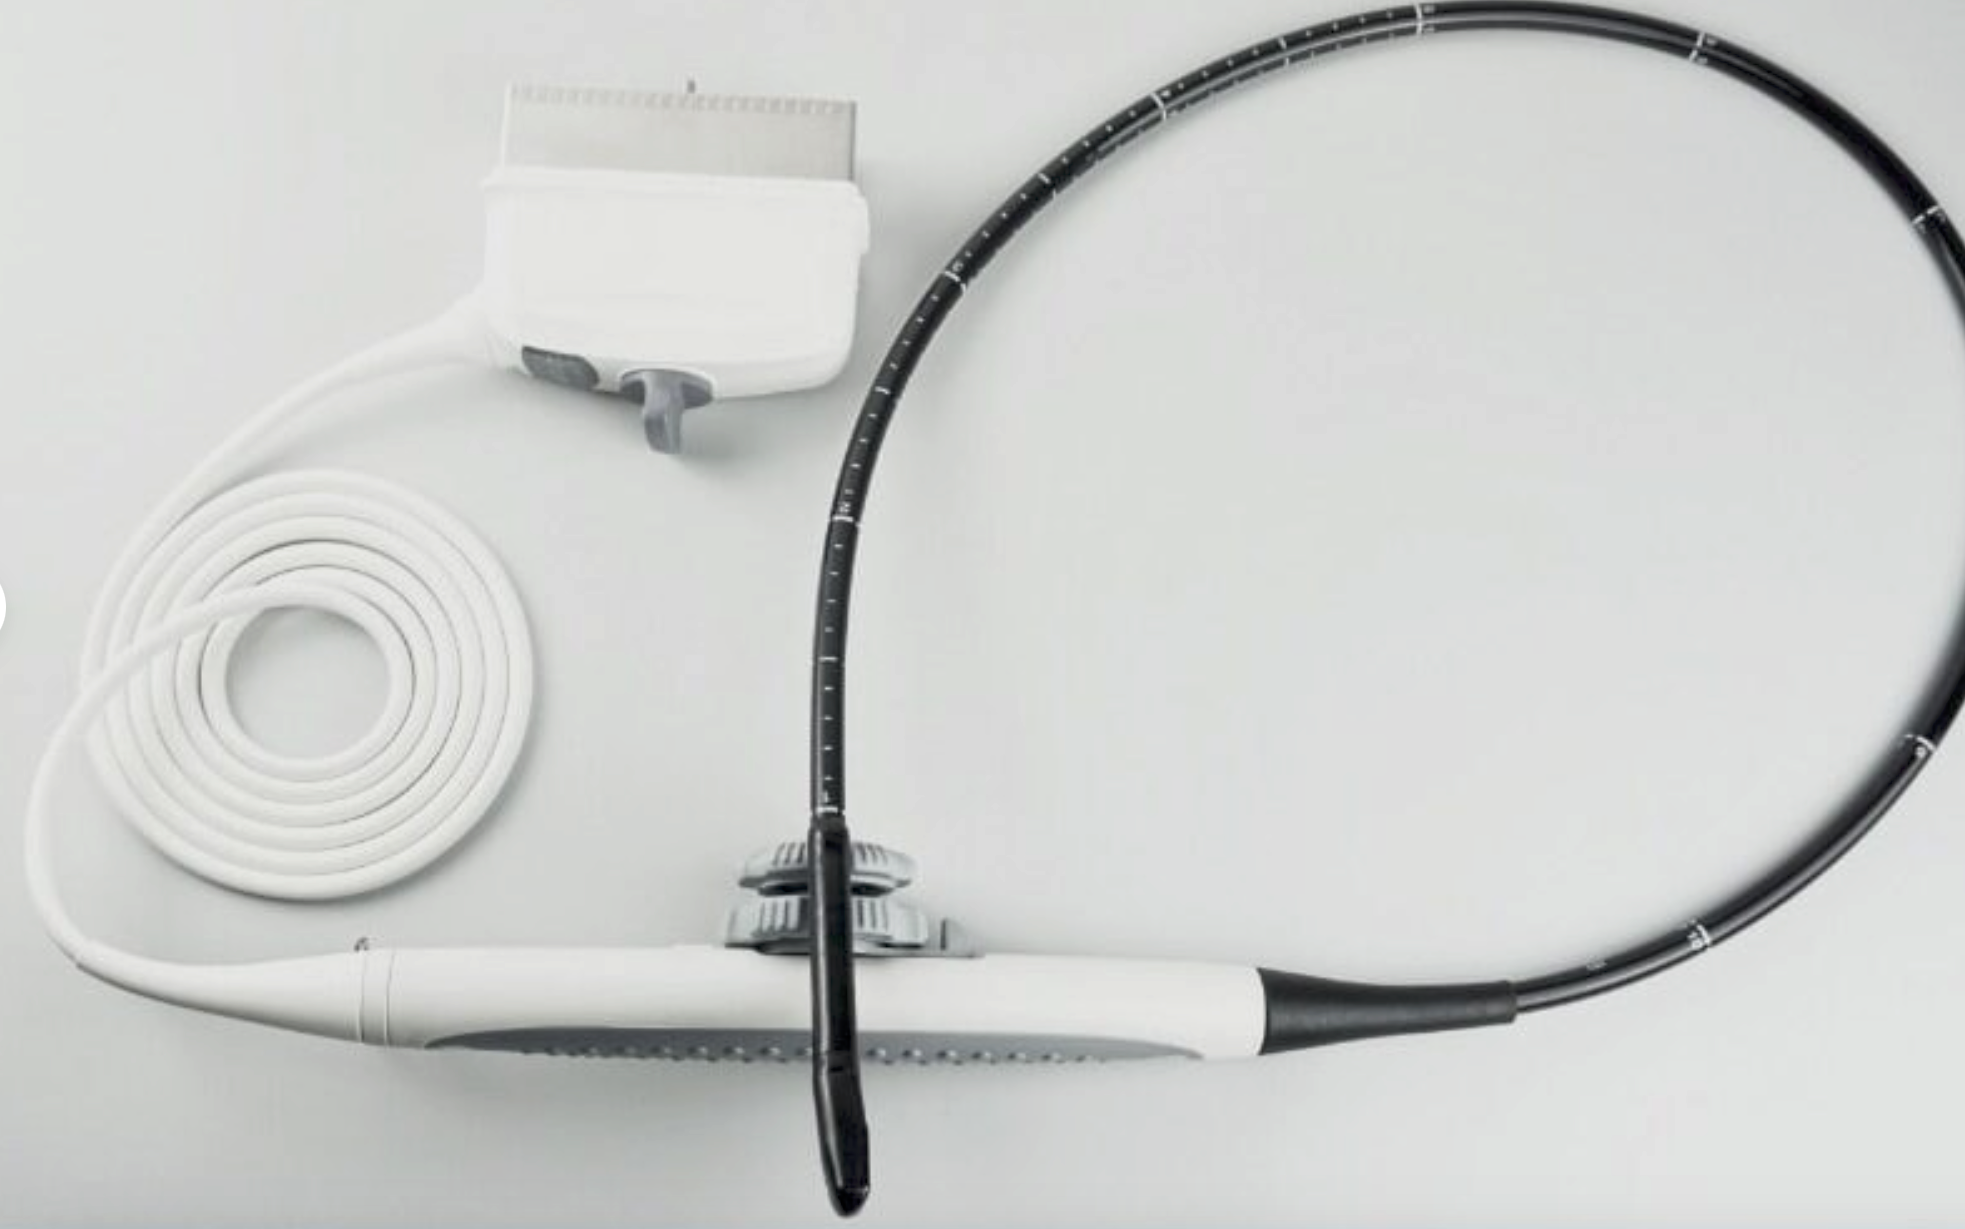

Digital Laptop External 3D Ultrasound Scanner+ Convex & Linear Probe 10" LCD CE 190891750662

Brand: Carejoy

Probe frequency: 2.5~10.0 MHz

probe connector: 1